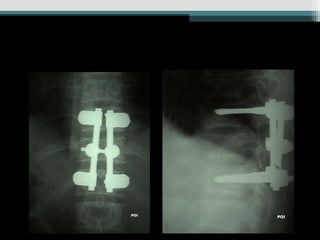

Caso 2 (25anos, auto, Fk a) www.traumatologiaeortopedia.com.b